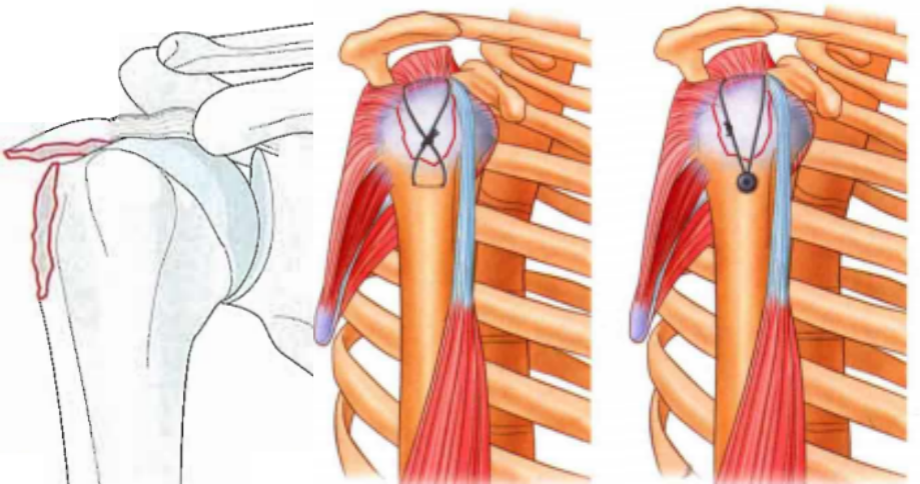

单纯大结节骨折移位较大甚至突入肱骨头及肩峰之间。

肱骨大结节骨折 ORIF,术前 X 线片显示肱骨大结节骨折情况;术中暴露肱

肱骨大结节骨折 ORIF,术前 X 线片显示肱骨大结节骨折情况;术中暴露肱